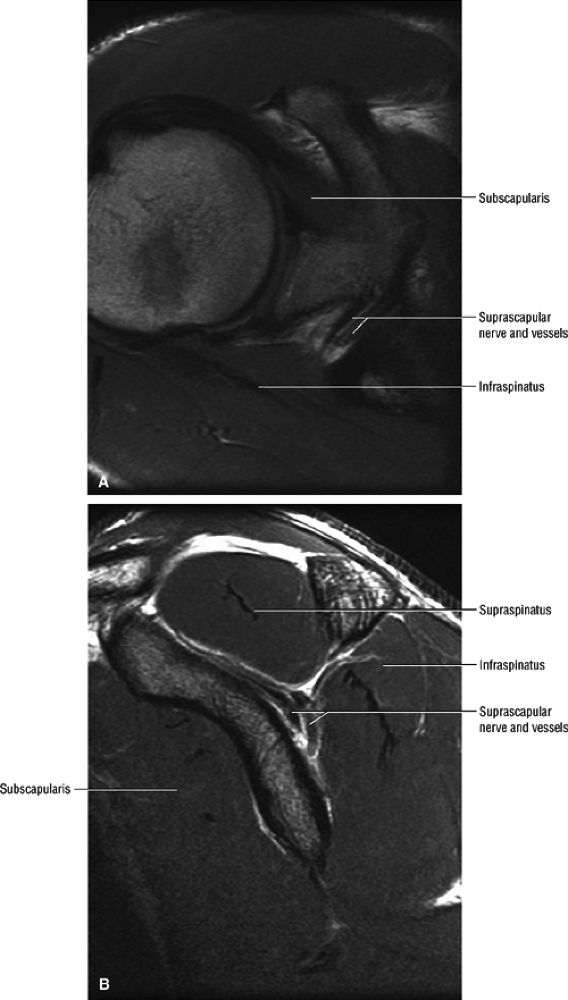

![]() |

FIGURE 12.2 ● The suprascapular nerve in the shoulder.

FIGURE 12.3 ● Normal MR anatomy of the suprascapular nerve. (A) Coronal PD-weighed image demonstrates suprascapular nerve and vessels outlined by fat within the spinoglenoid notch. The axillary nerve and vessels within the quadrilateral space are noted. (B) A more anterior coronal PD-weighed image demonstrates the suprascapular nerve and vessels outlined by fat within the suprascapular notch (or incisura).

FIGURE 12.4 ● Normal MR anatomy of the suprascapular nerve. (A) Axial PD-weighted image demonstrates the supra-scapular nerve as a linear, intermediate-signal structure at the level of the suprascapular incisura. (B) Sagittal PD-weighed image at the level of the spinoglenoid notch demonstrates the supra-scapular nerve and vessels.